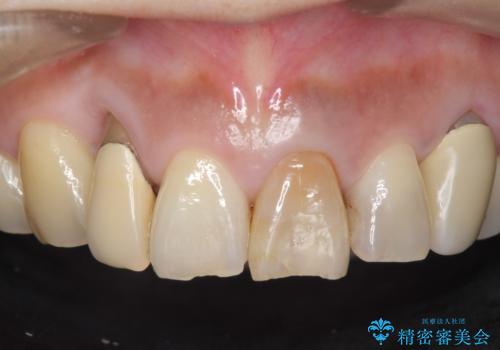

オールセラミッククラウン 下がってしまった前歯の歯茎の改善

- 他院で治療したところ、右上2番目の歯の歯茎が下がってしまったので診て欲しいといらっしゃった方の症例です。

診査の結果右上2は歯根が破折しており、それが原因で骨及び歯肉の吸収が起きていました。

このまま右上2の抜歯を行うとさらに歯茎が下がる恐れがあったため、歯の挺出によって骨レベルを回復した上で抜歯し、歯槽堤保存術(抜歯窩に人工骨を填入する手術)を行いました。

その後ブリッジによる補綴を行うことで、自然な見た目を再現することができました。